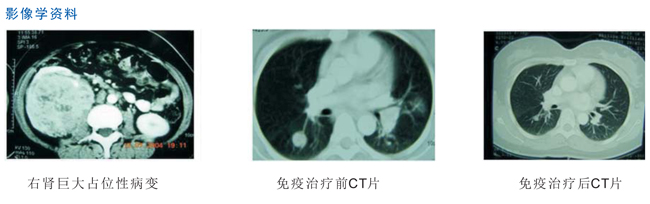

女,42歲,因檢查發(fā)現(xiàn)右腎占位入院。CT:右腎巨大占位性病變。雙肺可見多個(gè)結(jié)節(jié),考慮腎癌轉(zhuǎn)移。行右腎癌切除術(shù),術(shù)后病理:腎細(xì)胞癌2級(jí),下腔靜脈旁2枚淋巴節(jié)見腎細(xì)胞癌轉(zhuǎn)移。術(shù)后給予自體腫瘤細(xì)胞裂解物致敏樹突狀細(xì)胞皮下免疫12次,并聯(lián)合細(xì)胞因子誘導(dǎo)殺傷細(xì)胞(CIK)治療5次。復(fù)查胸部CT見多個(gè)轉(zhuǎn)移病灶消失。